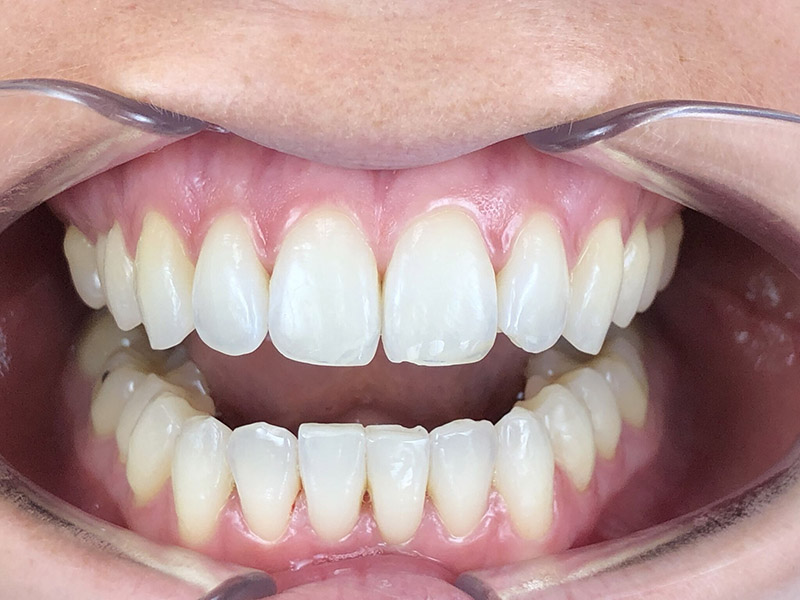

Patiente de 34 ans venue au cabinet pour une réhabilitation de son sourire suite à une récidive de son traitement d’orthodontie survenue pendant son adolescence, à cause du non-remplacement de sa contention perdue. Elle avait eu dans le passé une proposition de traitement par facettes pour réaliser l’alignement qu’elle avait refusé, ne voulant pas que l’on touche à ses dents.

À l’examen clinique, la patiente est en classe I d’Angle molaire bilatérale, indication idéale pour les traitements d’alignement simples que peuvent réaliser les omnipraticiens formés à cette thérapeutique.

Aucune autre pathologie ni problème dentaire ne furent relevés, en dehors d’un nettoyage préalable.

Comme on peut le constater, la durée du traitement n’aura pas excédé 10 mois au final, avec deux séries de gouttières, et un stripping relativement peu invasif pour que la patiente soit satisfaite du résultat. En ajoutant un blanchiment en ambulatoire, les dents ont retrouvé un aspect éclatant.